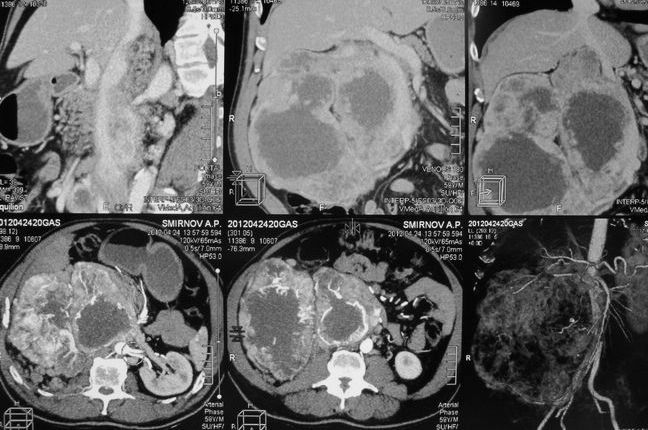

Опухоль правой почки (компьютерная томография)